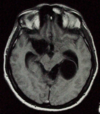

Size of tissue cysts in cysticercosis? where are they found?

A

1-2cm

Muscle (palpable) - eventually form calcified streaks

brain - seizures

7

Q

Most common cause of non-epileptic seizures worldwide

Neurocysticercosis